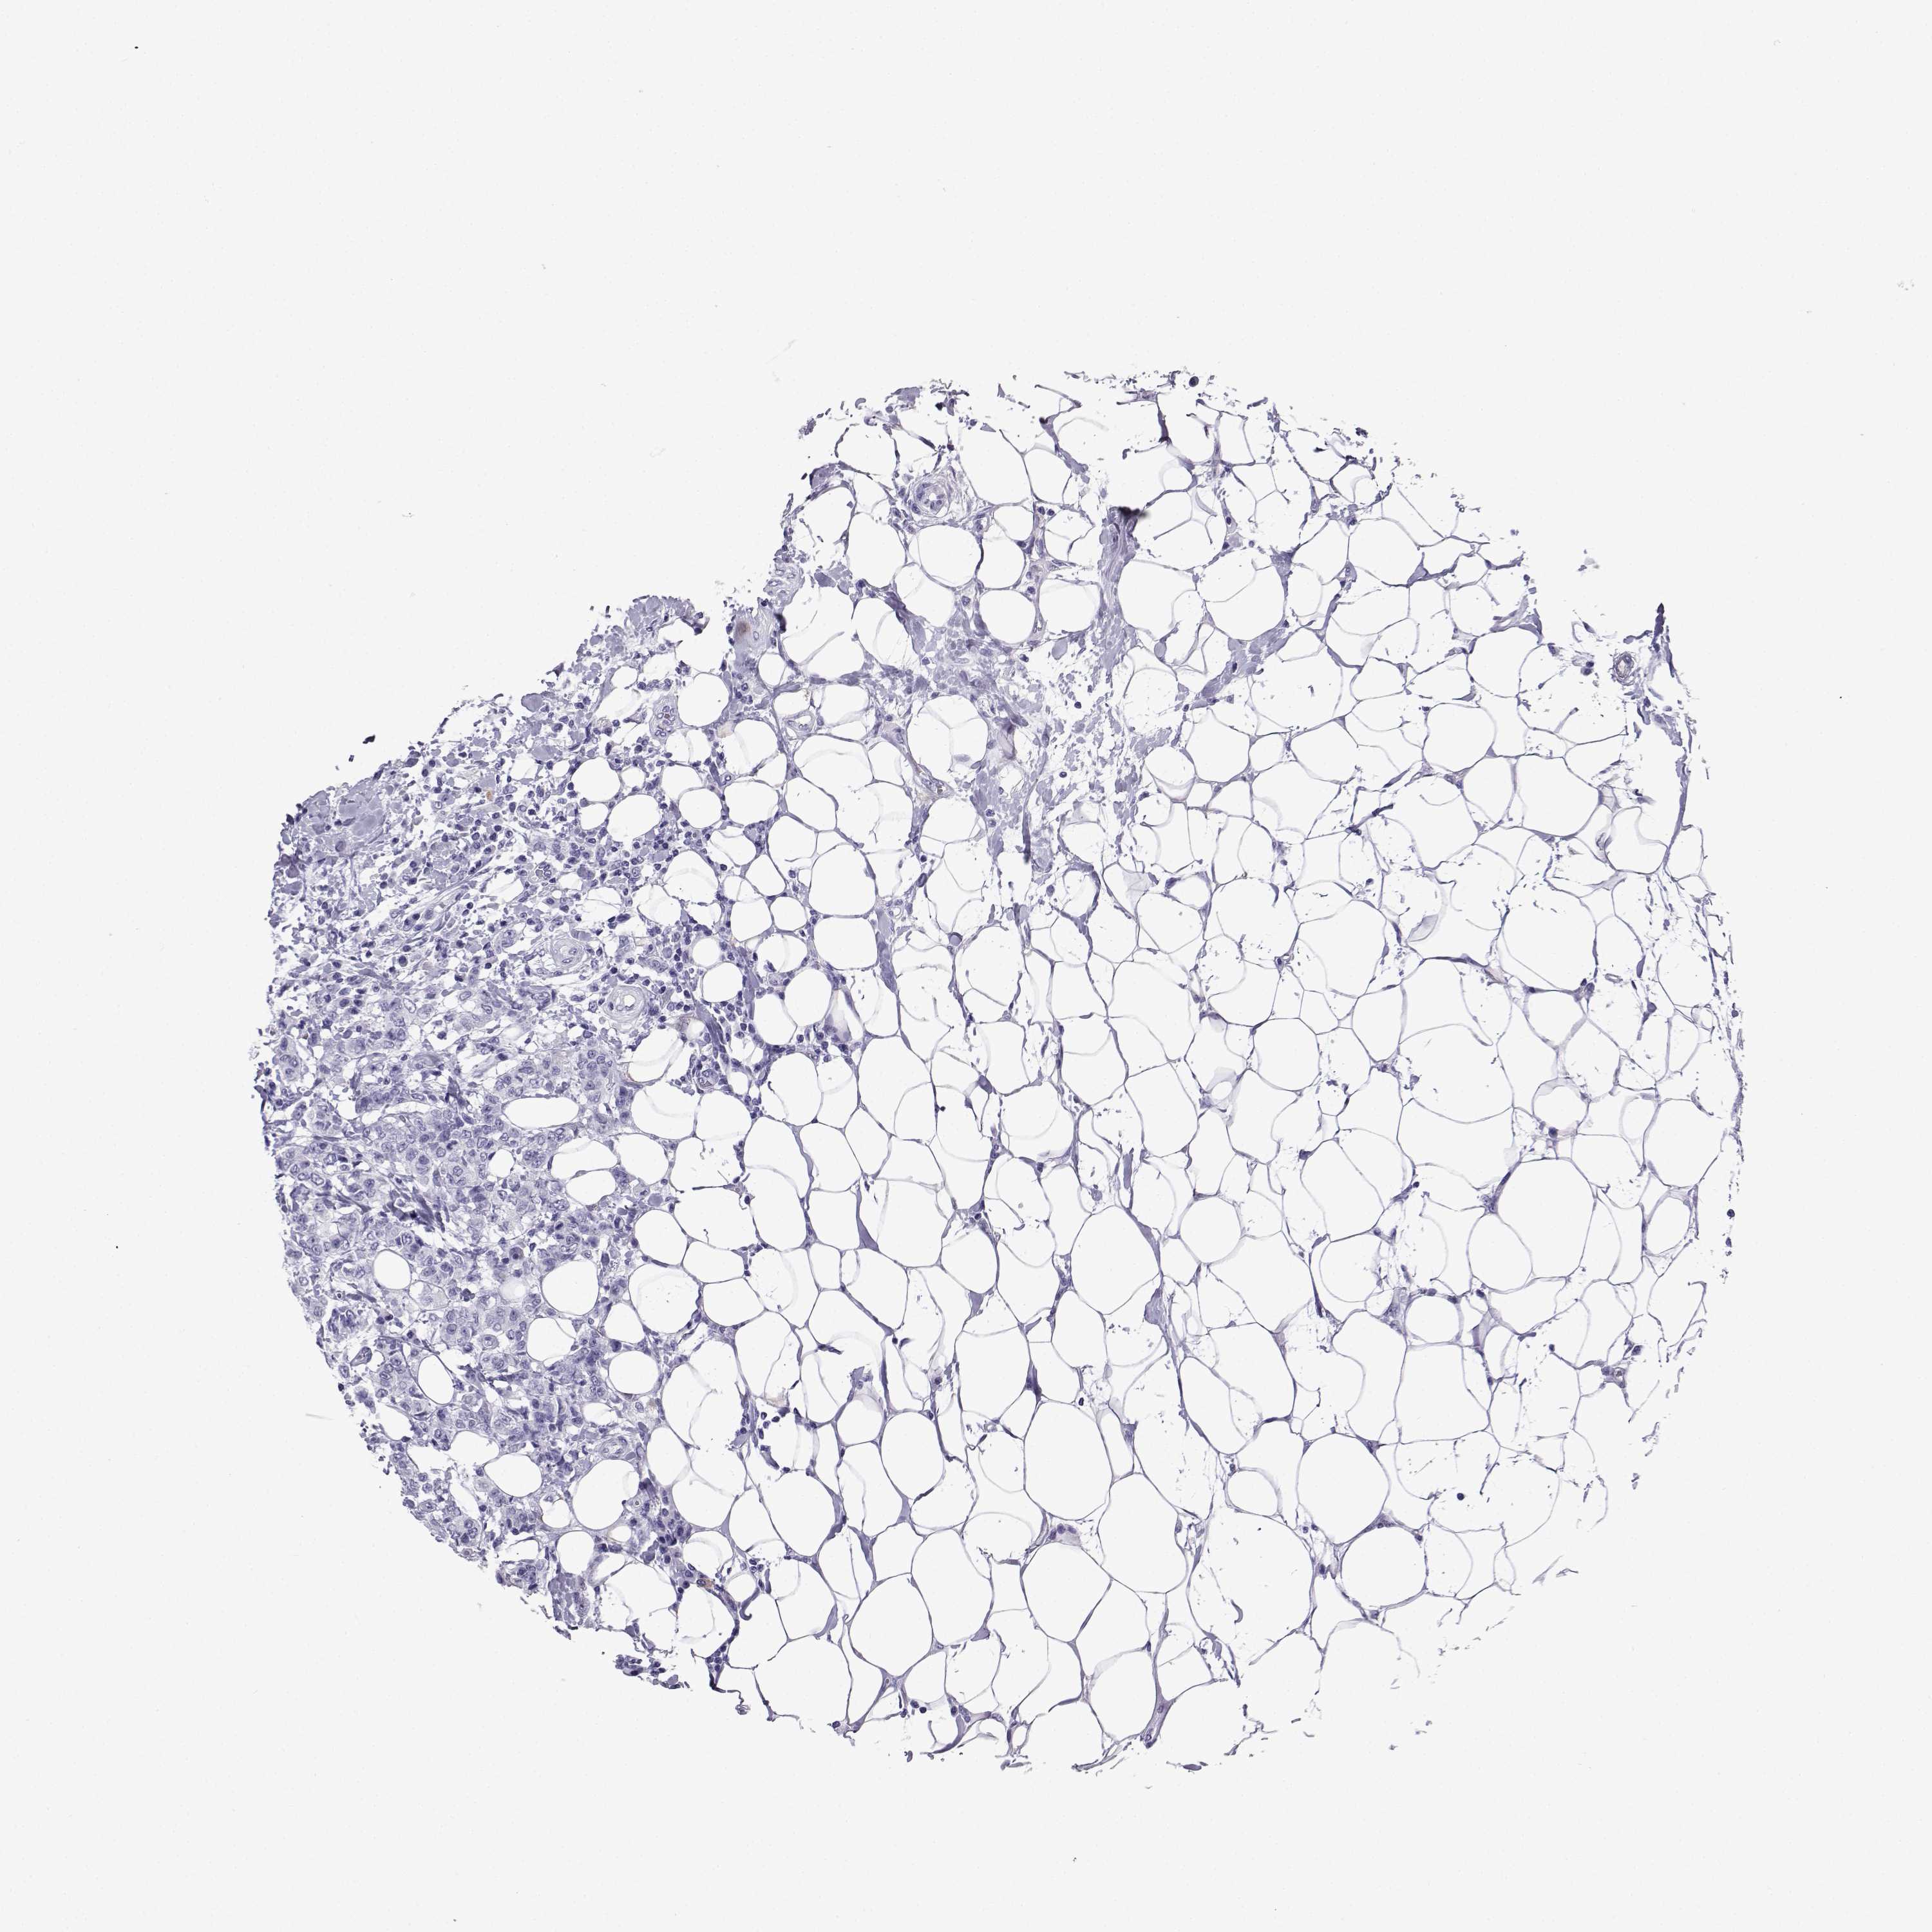

BRCA TCGA BRCA VALIDATION PROTEIN EXPRESSION

Breast cancer

Human cancer